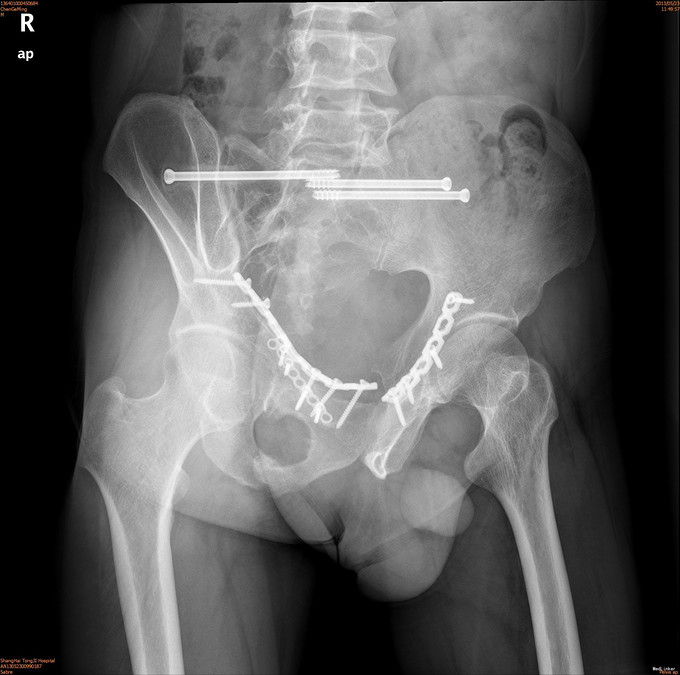

诊断为耻骨上下支骨折,兄弟科室会诊治疗结束后,患者病情稳定,行切开复位内固定术。

1年后随访患者无疼痛,活动可。耻骨上下支骨折ORIF术疗效良好。